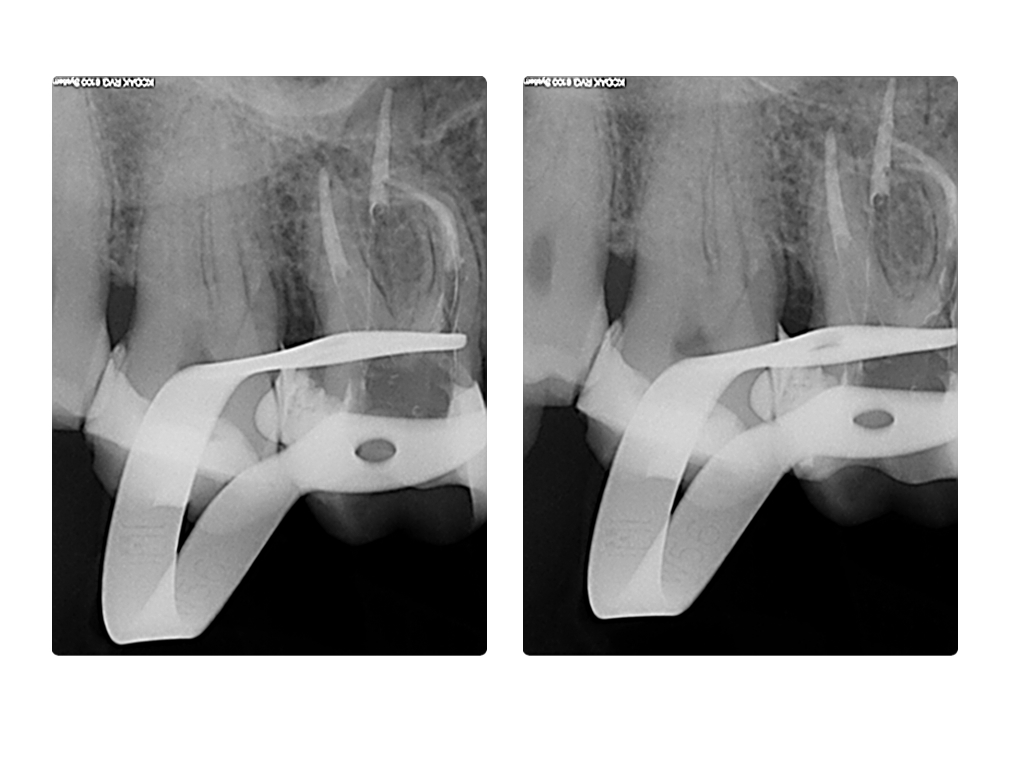

WS7.004

1024 × 768

Instrumentenfrakturen (2)